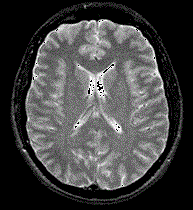

问题 患者,男,30岁,头痛、呕吐三周,低热,脑膜刺激征(+),MRI如图,最可能的诊断是 ( )

选项 A、HIV病毒感染脑损害 B、巨细胞病毒感染脑损害 C、真菌性脑膜炎 D、朊病毒感染所致脑损害 E、结核性脑膜炎

答案 A